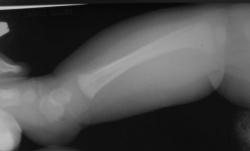

Ребенок 4 месяца. Отмечается увеличение размеров голени в течение нескольких месяцев после рождения. Травму, как бытовую, так и родовую мать отрицает. Мать обследована на ЗППП, в том числе сифилис. Выполнили рентгенографию, затем - КТ. Сначала думали о переломе и гипертрофической костной мозоли вследствие отсутствия иммобилизации, на реконструкции КТ видна как будто бы линия перелома (канал кровеносного сосуда?). Однако отсутствие положительной динамики со временем ("мозоль" не уменьшается) настораживает в плане возможной опухоли. Взяли открытую биопсию, материал пока еще в работе.

Уважаемый коллега! Еще раз пересмотрел изображения. И как это ни странно остался при первоначальном мнении, что это родовая травма. Возможно все-таки оказывалось какое-либо акушерское пособие? Все высказанное ранее - и "система", и сифилис полностью исключаются учитывая одностороннее поражение. В моей практике точно такого не было, но что-то подобное с меньшей "периостальной реакцией" было. Если предположить, что это неопластический процесс таких размеров, уже дико среагировала - бы кровь и другие показатели. С уважением Катенёв.

Опубликовано Валентин Катенёв в Сб, 01/24/2009 - 22:12. # Конечно, если-бы картинку обработать соответствующим образом, можно было-бы говорить более решительно, но на мой взгляд перелом не один, надо хорошо посмотреть дистальный метадиафиз. С большой степенью вероятности можно говорить о родовой травме. Интересно какое было предлежание плода и совершались-ли какие - либо акушерские мероприятия?

Опубликовано Валентин Катенёв в Сб, 01/24/2009 - 22:05. # Уважаемый коллега! Я совершенно не разбираюсь ни в КТ, ни в МРТ, ни в СКТ, ни в УЗИ. Но мне кажется, что в данном случае - см. вложение 11 четко дифференцируется косонаправленная прерывистость кортикального слоя б/берцовой кости - перелом? По всей видимости и гиперостоз и прочие изменения вызваны не диагностированным переломом.

Опубликовано Валентин Катенёв в Вс, 01/25/2009 - 14:28. # Уважаемая коллега! Полностью согласен с Вами по поводу "отслойки периостальных наслоений", возможно даже за счет излившейся крови (гематома). Такая махровость "периостальных наслоений" вполне может быть объяснена отсутствием иммобилизации, ибо ребенок постоянно двигает ножкой.